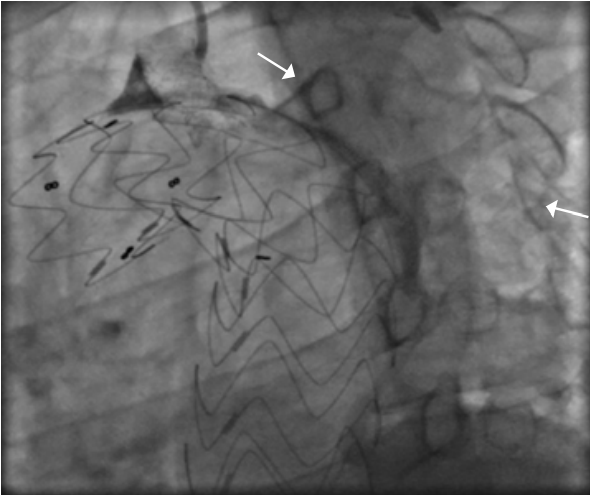

пЧКВ в течение 12 ч от начала ИМпST. В настоящее время получены убедительные доказательства того, что пЧКВ в течение 12 ч от начала ИМпST — лучший метод реперфузии при ИМпST. Обосновывая данное положение, далее будут приведены доказательства на основе анализа исследований сравнения пЧКВ с ТЛТ, сравнения пЧКВ с ФИС, сравнения пЧКВ с ФИС у пациентов в ранние сроки ИМпST.

пЧКВ после 12 ч от начала ИМпST при сохранении симптомов

Несмотря на то, что больные ИМпST с началом заболевания >12 ч при сохранении симптомов подозрительных в отношении ишемии миокарда, гемодинамической нестабильности или при наличии угрожающих жизни аритмий сердца отнесены к классу I рекомендаций для выполнения реперфузии при помощи стратегии пЧКВ, уровень достоверности данного утверждения основан на мнении экспертов. В качестве доказательства данного подхода используются только данные не нового исследования Gierlotka M, et al., 2011 [29], базирующегося на ретроспективном анализе польского регистра острого коронарного синдрома. Авторы сравнили результаты лечения больных ИМпST, поступивших через 12-24 ч после начала симптомов. Сравнивались консервативное ведение пациентов (n=1126) и стратегия пЧКВ (n=910). Через год после госпитализации смертность была достоверно выше в группе консервативного лечения (17,9% vs 9,3% при пЧКВ, Р<0,0001). Результаты в пользу стратегии пЧКВ сохранились и после дополнительного propensity-score matching анализа. Авторы заключили, что до проведения рандомизированных контролируемых исследований больные с ИМпST при госпитализации в поздние сроки могут рассматриваться на предмет проведения у них стратегии пЧКВ.

Несмотря на то, что анализ Gierlotka M, et al., 2011 [29] приводится в европейских рекомендациях 2017 и 2023гг [1, 7] как обоснование показаний к стратегии пЧКВ для "симптомных" больных ИМпST при госпитализации после 12 ч от начала симптомов, в самом исследовании Gierlotka M, et al. изучали больных только со сроками госпитализации 12-24 ч от начала симптомов. Поэтому данное исследование, конечно, не вполне корректно использовать в качестве доказательства пользы пЧКВ после 12 ч от начала симптомов и в т.ч. за пределами 24 ч. Тем не менее с клинических позиций традиционной кардиологии рекомендации по применению стратегии пЧКВ у симптомных пациентов несмотря на поздние сроки госпитализации выглядят вполне логичными.